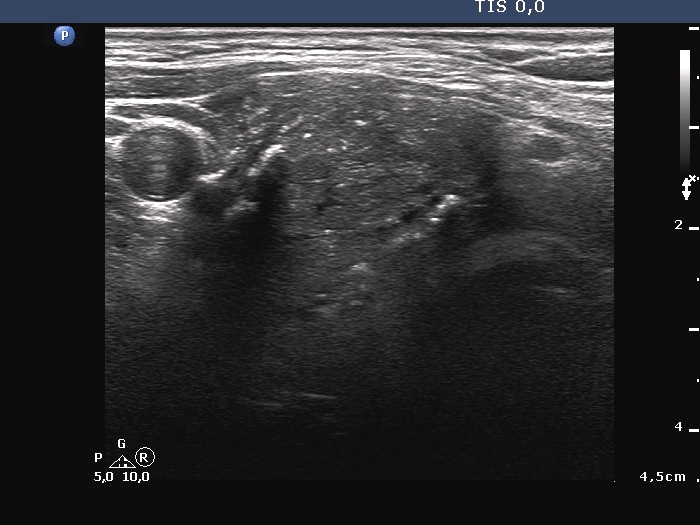

Ultrasonography. The thyroid was echonormal. A large hypoechoic nodule occupied almost the entire right lobe. The nodule showed various intranodular echogenic figures, including microcalcifications, macrocalcification and non-specific figures. The borders were indistinctive. The lesion was suspicious spreading extrathyroidal.